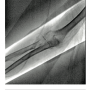

The right radial artery was punctured using counter-puncture technique and a .021-inch micropuncture guide wire was placed in the Teflon cannula. Mild difficulty was encountered at the first attempt to advance the wire. The guide wire was withdrawn and a low-pressure manual injection radial angiogram was performed. A perforation was noted at the distal radial artery (Figure 1). In an attempt to obtain control of the radial artery lumen, a .014-inch guide wire was placed in the access cannula and attempts were made to navigate the lumen, with further resistance. A new area of perforation was noted proximal to the previous site of extravasation (Figure 2). After several attempts, the .014-inch guide wire was placed in the subclavian artery successfully. Tortuosity was noted all along the proximal vessels (Figure 3).

The most common etiology of radial artery perforation is guide wire-related trauma. A J-tipped guide wire ‘engaging” a small side branch is frequently presumed to be a cause for “cryptogenic” perforations. In this instance, difficulty in advancing the guide wire with likely side branch trauma or subintimal placement would have resulted in perforation. As recommended, the operators performed a radial angiogram when they encountered resistance to advancement of the guide wire (Figure 1). Appropriately so, instead of abandoning the access site, they elected to gain control of the arterial lumen and succeeded (Figure 3).1,2 Perforation being the immediate issue at hand, a catheter was placed through the perforated segments and the procedure was